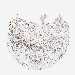

LIVER CANCER - Protein expressioni

A mouse-over function shows sample information and annotation data. Click on an image to view it in a full screen mode. Samples can be filtered based on level of antibody staining by selecting one or several of the following categories: high, medium, low and not detected. The assay and annotation is described here.

Antibody stainingi

Antibody staining in the annotated cell types in the current human tissue is reported as not detected, low, medium, or high, based on conventional immunohistochemistry profiling in selected tissues. This score is based on the combination of the staining intensity and fraction of stained cells.

Each image is clickable and will lead to virtual microscopy that enables deeper exploration of all samples and also displays staining intensity scores, fraction scores and subcellular localization as well as patient and tissue information for each sample.

Antibody HPA008208

Antibody HPA011389

Staining

High

Medium

Low

Not detected

Intensity

Strong

Moderate

Weak

Negative

Quantity

>75%

75%-25%

<25%

None

Location

Nuclear

Cytoplasmic/membranous

Cytoplasmic/membranous,nuclear

Cholangiocarcinoma

Carcinoma, Hepatocellular, NOS